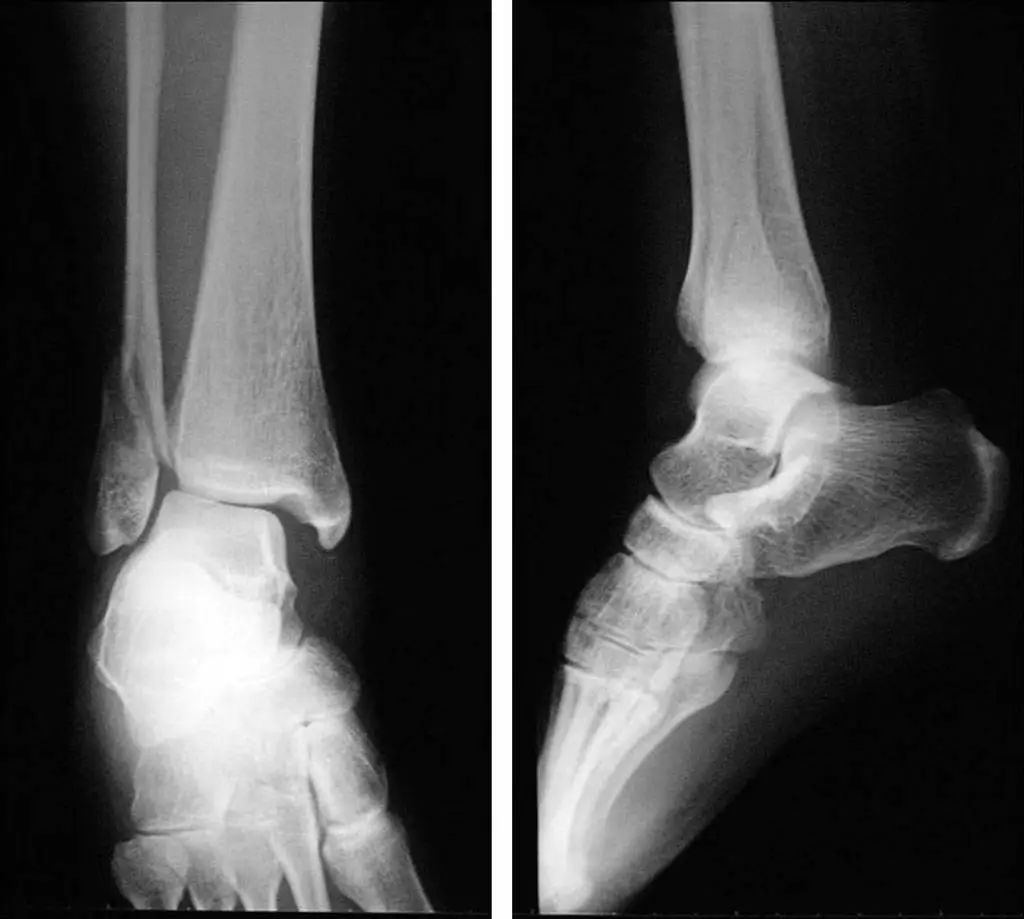

Lorsque l'articulation de la cheville est gravement blessée, la cheville interne et externe et le talus seront déplacés à 11 degrés différents (Figure 11).Les radiographies statiques ne reflètent pas avec précision la stabilité de l'articulation de la cheville.Les radiographies de stress et l'IRM peuvent améliorer l'évaluation de la stabilité de l'articulation de la cheville et des lésions ligamentaires (Figure 12).

Figure 12 Radiographie de stress (rupture du ligament triangulaire)